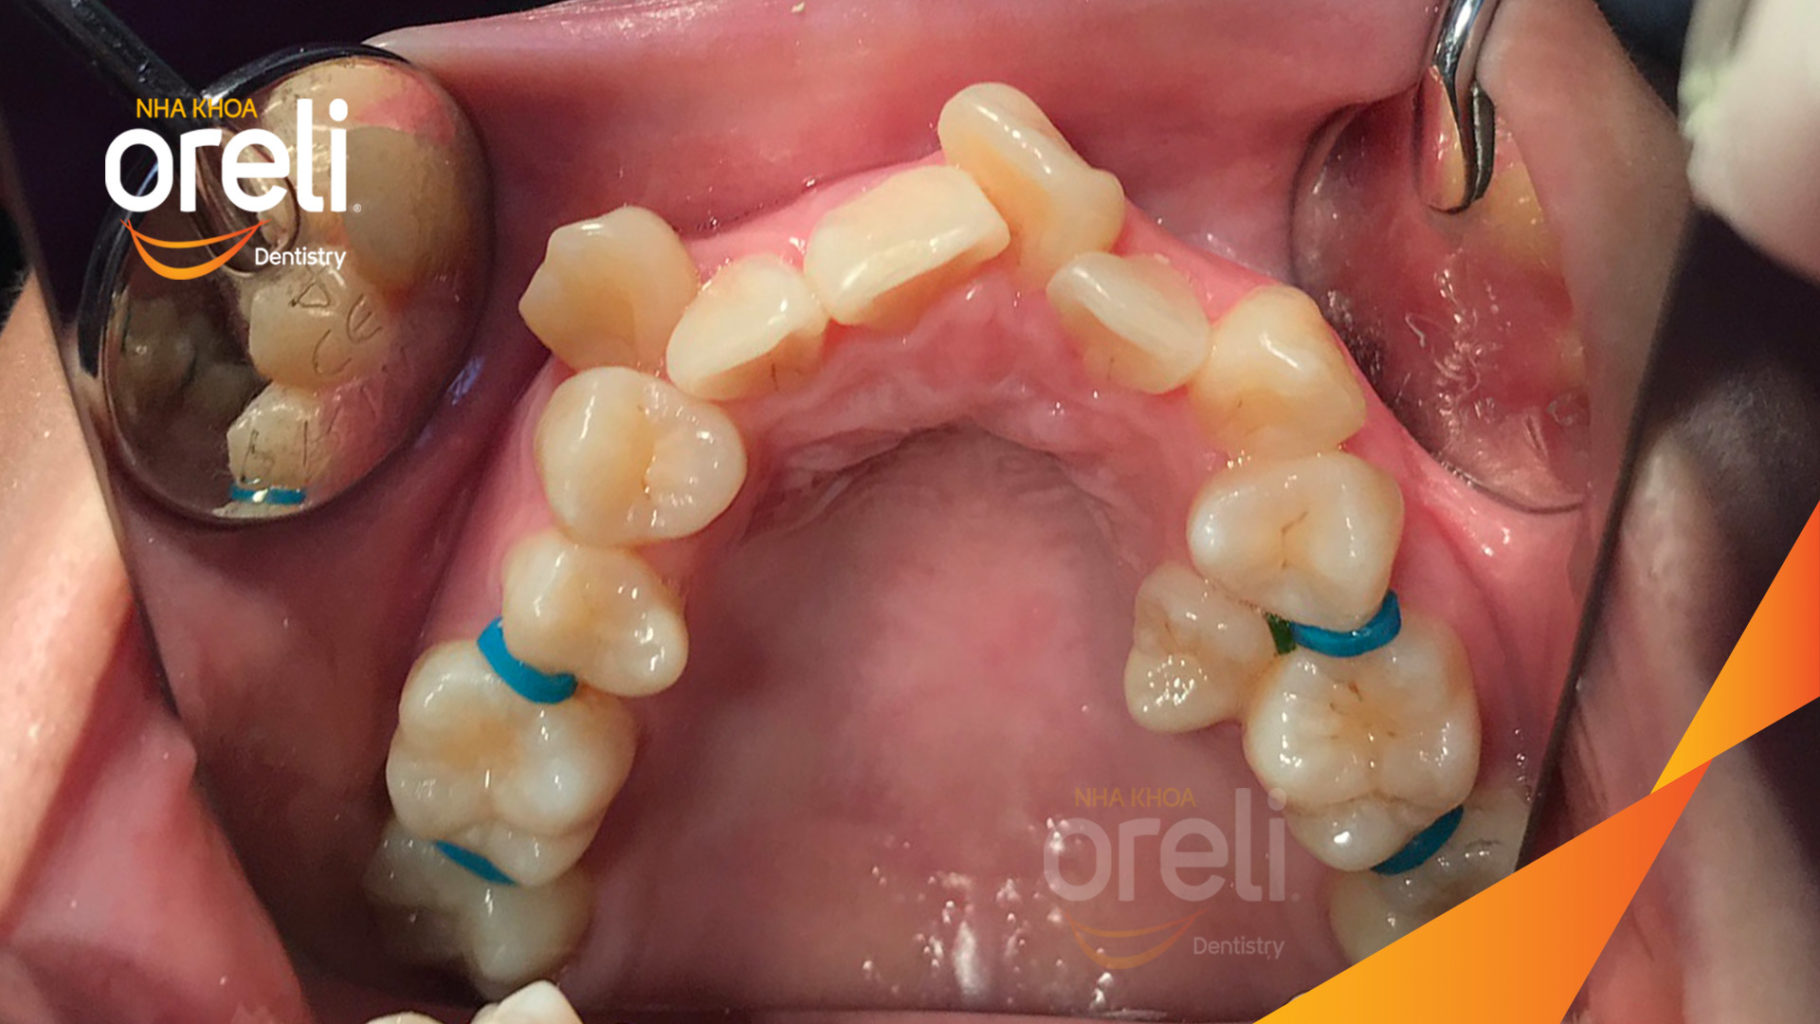

Ca niềng chỉnh chen chúc hẹp hàm nặng cả trên và dưới – Kết quả điều trị thực tế tại nha khoa Oreli

Ca niềng răng chen chúc phục hồi ăn nhai và thẩm mỹ nụ cười. Kết quả thực tế trước và sau điều trị tại Nha khoa Oreli.

Hình ảnh thực tế